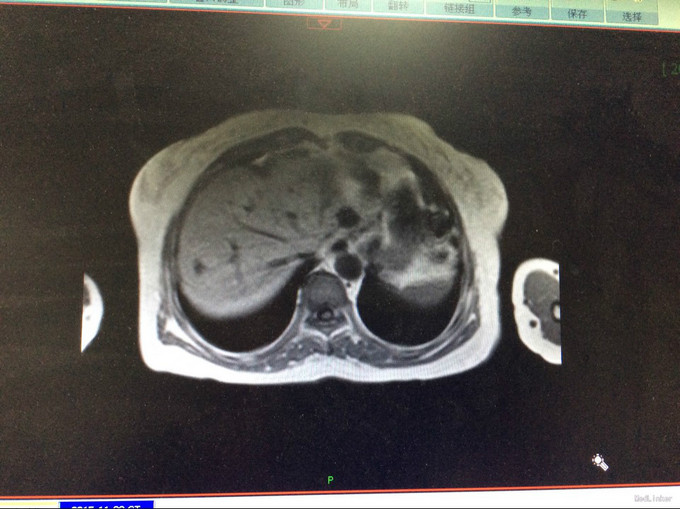

查体:生命体征平稳。神智清,查体合作,面容正常,淋巴结未触及肿大。双肺听诊呈清音,为闻及干湿罗音及哮鸣音;心率78次/分,律齐,无异常心音及心脏杂音;腹平软,肝脾肋下未及,未触及肿块,无压痛及反跳痛,肠鸣音正常。双下肢无水肿,生理反射存在,病理反射未引出。专科查体:无明显异常。辅助检查:湖北省中医院CT示:胰腺占位。CT检查示:1.结合原CT、MR检查,胰腺体尾部及周围异常改变,考虑胰腺炎伴坏死囊性变可能性大,与2015-11-20CT相比较,囊性病变略缩小;腹膜后淋巴结增多增大,大致同前;2. 所及肝脏多发囊肿;肝右叶后段其中一个病变边缘可疑强化,大小与前次相仿;3. 左侧肾上腺饱满。 MRI检查示: 胰腺体尾部及周围异常改变,考虑胰腺炎伴坏死囊性变可能性大,合并肿瘤性病变待排,病变累及腹膜伴腹膜后淋巴结增多增大,腹腔少许积液,请结合检查结果考虑;2. 所及肝脏多发囊肿;肝右叶后段其中一个病变边缘可疑强化,需鉴别于血管瘤与转移性病变,建议随访复查;3. 左侧肾上腺饱满;4. 所及右侧胸廓外小结节(层面16-7),直径约4mm,不除外右乳的病变:5. 所及腰椎骨性纵裂畸形。病理检查:(胰体尾部肿块穿刺组织)高分化腺癌,考虑为IPMN相关性浸润性癌。